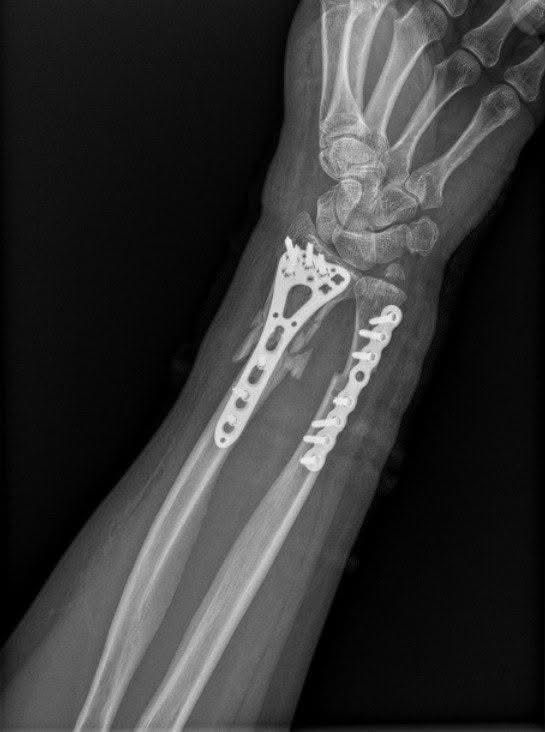

The funds will be used to procure mechanical fixation systems and implants essential for bone reconstruction and stabilization, including osteosynthesis implant kits, spinal stabilization systems, joint endoprostheses, and other surgical materials. SVOYI will handle the direct purchase and distribution of these components to hospitals treating wounded patients across Ukraine.

The primary treatment for severe bone damage is osteosynthesis—a procedure involving precise repositioning and fixation of bone fragments using mechanical implants. This approach is crucial to preserving limb functionality and enabling recovery for patients.